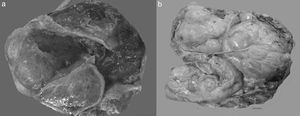

Desde el punto de vista macroscópico, constituyen tumores sólidos que tienden a conservar la forma general de los ovarios; su superficie es lisa, irregularmente esférica, aunque puede ser francamente nodular. Además, aunque hayan alcanzado un tamaño considerable, están generalmente propensos a quedar libres, sin adherencias a estructuras circundantes, son de tamaño promedio de 10cm y rara vez exceden los 20cm. En la superficie de corte son predominantemente blanco grisáceo o amarillo pálido, con frecuentes áreas de coloración café o roja en presencia de necrosis o hemorragia. Presentan una consistencia firme, carnosa (esponjosa) o gelatinosa, lo que depende de la cantidad de edema o mucina dentro del estroma, de la hipercelularidad estromal y de la fibrosis (fig. 2)3,5,8,16,27.